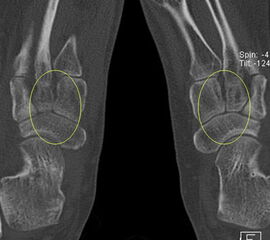

Die Abbildungen 4.2.a bis d zeigen den typischen Aspekt einer talacalcanearen Coalitio. Es besteht nur eine linksseitige, symptomatische Coalitio talocalcaneare (4.2.a und c); das 35 Tage zuvor angefertigte MRT zeigt keine auffälligen Signalveränderungen (4.2.b und d).

Abbildung 4.3. zeigt die Ursache für rechtsseitige Sprunggelenksbeschwerden bei einem Patienten mit talocalcanearen Coalitionen: nur die osteochondrale Läsion an der distalen rechten Tibia ist die Ursache des Schmerzes. Die bilateralen talocalcanearen Coalitionen sind asymptomatisch.